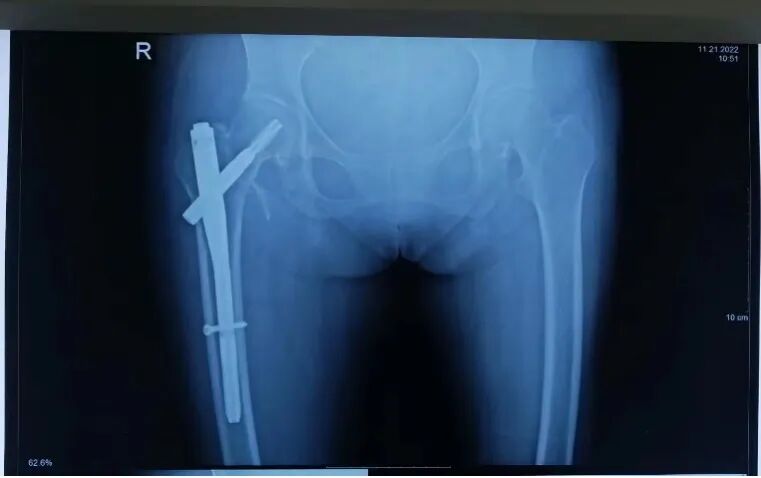

近日,微山湖医院骨一科收治了一名75岁的女性患者。患者在家中行走时不慎摔倒,当时就感到右髋部疼痛剧烈,不能站立,无法行走。入院完善相关辅助检查后,明确诊断为“股骨粗隆间粉碎性骨折”。由于患者年纪较大,骨折粉碎较重,手术难度大,在邀请多学科会诊评估心肺功能,排除手术禁忌后,骨一科团队经过多方位讨论,制定了精准周密的手术方案,于2022年11月10日顺利完成手术,患者术后恢复良好,仅仅三天就能在助行器保护下下地。该手术具有创伤小、恢复快等特点,为老年人有效治疗骨折打开了一条新道路!

(术前)

(术后)